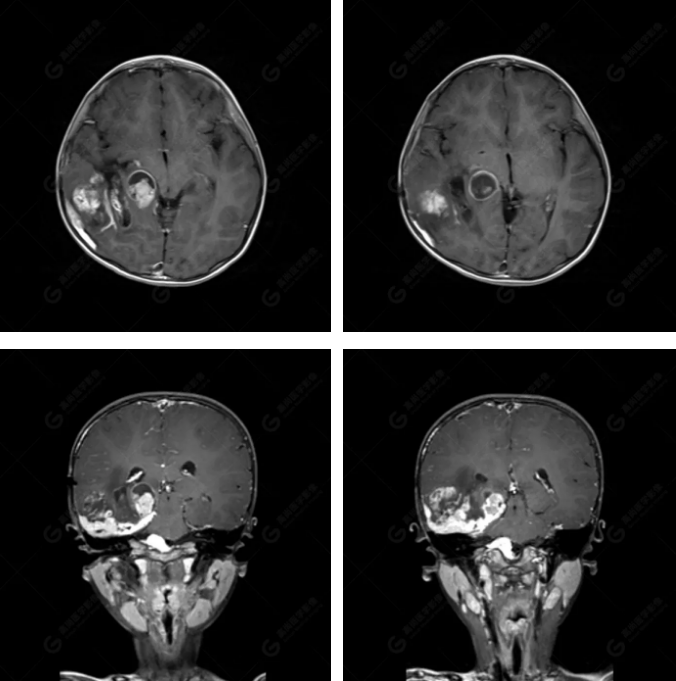

右側(cè)顳葉腫瘤切除術(shù)后(具體不詳):右側(cè)顳部骨質(zhì)不連續(xù)呈術(shù)后改變,右側(cè)顳葉術(shù)區(qū)見(jiàn)片狀長(zhǎng)T1長(zhǎng)T2信號(hào)影,F(xiàn)LAIR呈低信號(hào);術(shù)區(qū)后方右側(cè)顳枕葉見(jiàn)一巨大占位性病變影,邊界欠清,大小約6.2×5.8×4.3cm(前后×左右×上下),信號(hào)不均勻,T1WI呈等稍低信號(hào)間雜少許高信號(hào),T2WI呈高稍低混雜信號(hào),DWI示部分病灶彌散受限,相應(yīng)ADC圖減低,磁敏感序列見(jiàn)部分呈極低信號(hào),增強(qiáng)掃描可見(jiàn)明顯不均勻強(qiáng)化,鄰近硬腦膜及小腦幕增厚并明顯強(qiáng)化;另延髓右前方及右側(cè)橋小腦角區(qū)見(jiàn)一不規(guī)則形異常信號(hào)影,大小約3.2×1.3×3.7cm(左右×前后×上下),呈長(zhǎng)T1稍長(zhǎng)T2信號(hào),F(xiàn)LAIR呈等信號(hào),DWI未見(jiàn)受限,增強(qiáng)后明顯均勻強(qiáng)化,鄰近腦膜明顯強(qiáng)化。鄰近腦實(shí)質(zhì)及右側(cè)顳角明顯受壓;左側(cè)大腦半球未見(jiàn)局灶性信號(hào)異常,中線結(jié)構(gòu)稍左移。

右側(cè)顳葉腫瘤切除術(shù)后:現(xiàn)術(shù)區(qū)后方右側(cè)顳枕葉及延髓右前方占位,右側(cè)顳枕部硬腦膜及小腦幕明顯強(qiáng)化,結(jié)合既往影像資料,考慮為胚胎源性惡性腫瘤,如非典型畸胎樣/橫紋肌樣瘤(AT/RT)或原始神經(jīng)外胚層腫瘤(PNET)。

非典型畸胎樣/橫紋肌樣瘤(AT/RT) 是一種高度惡性中樞神經(jīng)系統(tǒng)腫瘤,臨床罕見(jiàn),臨床表現(xiàn)無(wú)特異性,好發(fā)于 5 歲以下兒童,尤以 3 歲以下多見(jiàn),在兒童原發(fā)性中樞神經(jīng)系統(tǒng)(CNS)腫瘤中占 1%~3%。該腫瘤體積一般較大,幕上大于幕下,有明顯的占位效應(yīng)。該腫瘤成分復(fù)雜,囊變、出血、壞死常見(jiàn)。因此 AT/RT信號(hào)混雜,囊性部分呈 T1WI低、T2WI高信號(hào),增強(qiáng)后不強(qiáng)化;若瘤體出血,囊內(nèi)可見(jiàn)T1WI稍高信號(hào)、T2WI低信號(hào),實(shí)性部分在 T1WI上呈混雜等、低信號(hào),在T2WI 及 T2-FLAIR上呈混雜等高信號(hào),增強(qiáng)掃描后大部分呈環(huán)形條帶樣明顯強(qiáng)化,中心壞死區(qū)不強(qiáng)化。另外,該腫瘤實(shí)性成分在DWI上呈高信號(hào),說(shuō)明腫瘤細(xì)胞核密集,水分子擴(kuò)散明顯受限,提示該腫瘤惡性程度高,容易復(fù)發(fā)及轉(zhuǎn)移。